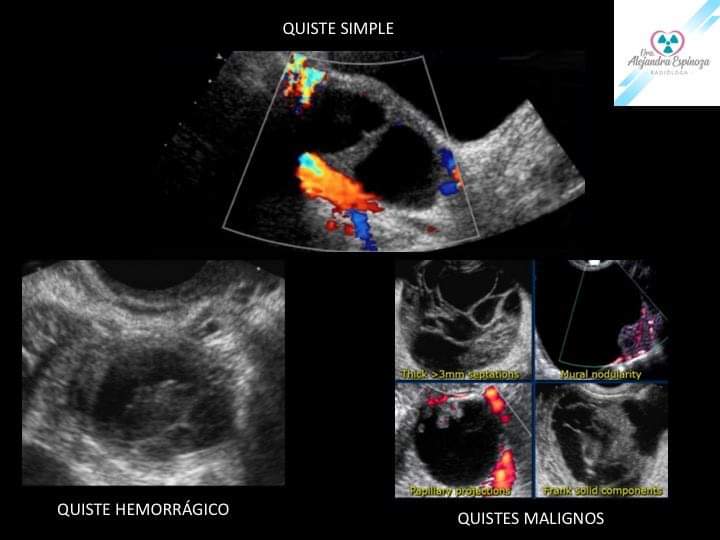

Masas Ovaricas

Dra, Alejandra Espinoza Esp. en Radiología e Imagenología Resonancia Magnética Cardiovascular Centro de Diagnóstico Por Imágenes “Linda Vista”